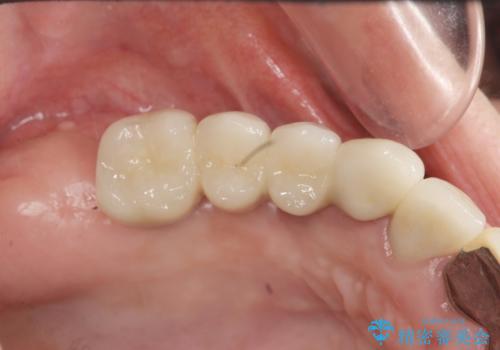

- 120万円(インプラント×3 チタンカスタムアバットメント×3 メタルボンドクラウン×3 骨造成 歯肉移植)費用は治療当時の料金となります

インプラントが長持ちするために、インプラント周囲の十分な骨量・角化歯肉の存在・安定した咬合を一つづつ整備する治療を行いました。